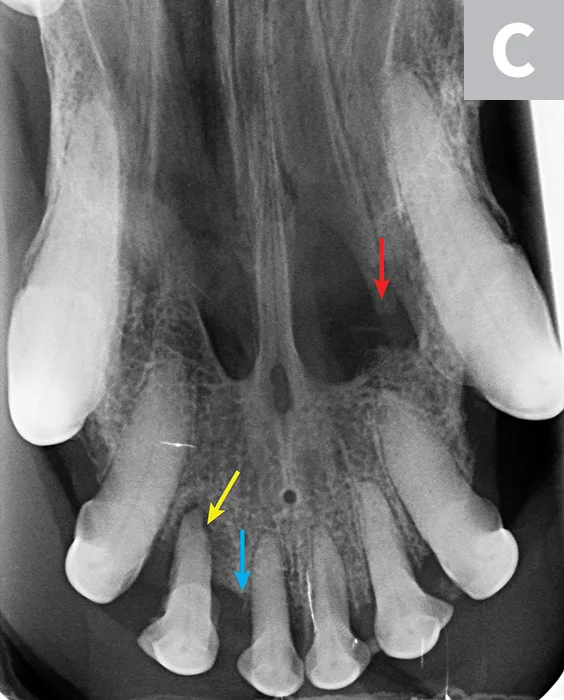

Three dental radiographs.

Figure 2

Dental radiographs of the right (A) and left (B) maxillary canine teeth (lateral views) and the rostral maxillae (C; occlusal view) confirmed mild horizontal and severe vertical bone loss at the mesial aspect of both maxillary canine teeth. Moderate to severe horizontal bone loss at the right maxillary first incisor tooth (blue arrow) and total loss of attachment with inflammatory root resorption at the right maxillary second incisor tooth (yellow arrow) were present. The remaining maxillary incisor teeth were affected by mild horizontal bone loss. Although the occlusal view of the rostral maxillae is slightly asymmetric, osteolysis was evident in the area of the left palatine fissure (red arrow). Mild horizontal bone loss was diagnosed at several other teeth. In addition, retained root tip of the left maxillary (presumably) first premolar tooth (white arrow) was identified.